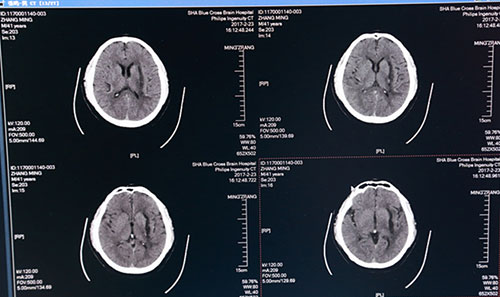

术后第二日头颅CT:血肿基本清除,红圈内白色光点为穿刺针

术后一周头颅CT:血肿术后改变,血肿清除干净

全脑血管造影(DSA)图像:红圈内为出血部位,血管未见异常

术后第二日,复查头颅CT示:左侧基底节区血肿已基本清除干净,术后一周再次复查头颅CT示:左侧基底节区血肿术后改变,血肿已基本清除,蛛网膜下腔渗出较前减少,金属引流管撤除;术后一月复查全脑血管造影(DSA),出血点血管未见异常,排除脑动脉瘤破裂出血可能。目前患者精神奕奕,正在积极接受康复综合治疗,不日即可出院,回归正常生活。